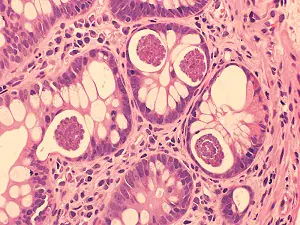

2018 DPDx Case Studies

DPDx is an educational resource designed for health professionals and laboratory scientists. For an overview including prevention, control, and treatment visit www.cdc.gov/parasites/.